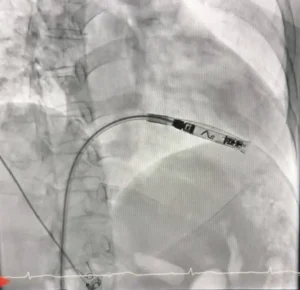

ผู้ป่วยเป็นหญิงอายุ 56 ปี ได้รับการวินิจฉัยว่าเป็นโรคหัวใจเต้นช้าผิดจังหวะชนิดสมบูรณ์ (Complete Heart Block) ซึ่งจำเป็นต้องใส่เครื่องกระตุ้นหัวใจเพื่อช่วยควบคุมจังหวะการเต้นของหัวใจ โดยคณะแพทย์ได้เลือกใช้เครื่องกระตุ้นหัวใจชนิดไร้สาย (Leadless Pacemaker) ซึ่งเป็นเทคโนโลยีใหม่ล่าสุด ทำการใส่ผ่านสายสวนหลอดเลือดเข้าสู่หัวใจโดยตรง

เทคโนโลยีดังกล่าวมีข้อดีคือ ไม่มีสายไฟเชื่อมต่อกับตัวเครื่อง ลดความเสี่ยงต่อการติดเชื้อ ลดภาวะแทรกซ้อนจากสายเครื่องกระตุ้นหัวใจ และช่วยให้ผู้ป่วยฟื้นตัวได้เร็วขึ้น